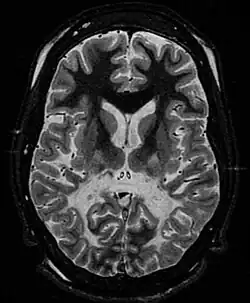

White matter, with reduced volume and increased signal intensity. The anterior white matter is spared. Features are consistent with X-linked adrenoleukodystrophy.

The Loes score is a rating of the severity of abnormalities in the brain found on MRI. It ranges from 0 to 34, based on a point system derived from the location and extent of disease and the presence of atrophy in the brain, either localized to specific points or generally throughout the brain. A Loes score of 0.5 or less is classified as normal, while a Loes score of 14 or greater is considered severe. It was developed by neuroradiologist Daniel J. Loes MD and is an important tool in assessing disease progression and the effectiveness of therapy.[19]